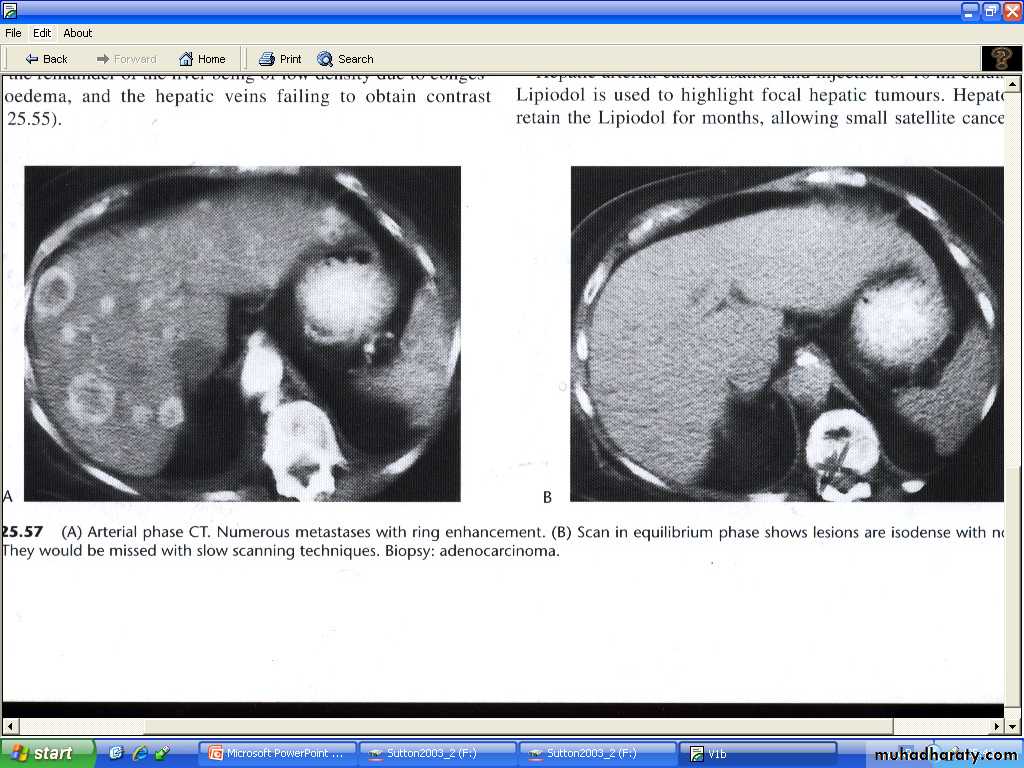

CT

# usually seen as lower density than the contrast enhanced surrounding liver parenchyma.

# intense contrast enhancement some time seen within the tumor or immediately surrounding them- a useful differentiating feature , which is not seen with cysts.

# some metastases ( e.g. carcinoid )are hypervascular and appear as high density areas.

Most metastases are best demonstrated at portal phase as areas of low attenuation"hypodense" .

Scanning during arterial phase will shows lesions such as haemangiomas ( has typical enhancement pattern – discuss later ) and highly vascular metastases , as areas of grater enhancement than surrounding parenchyma